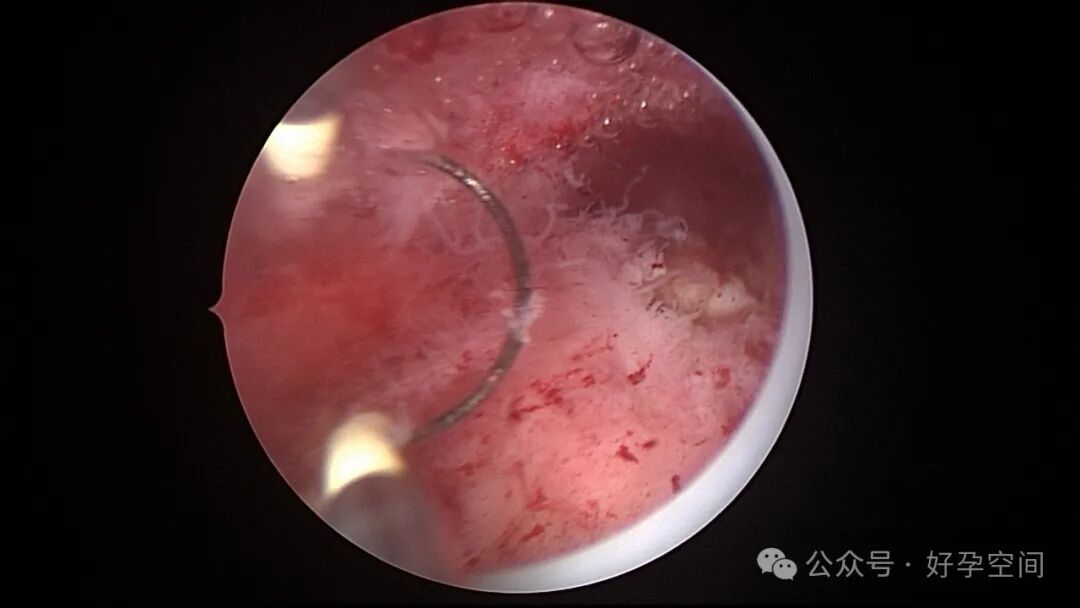

从以上病例可知,人流不全、药流不全有时候难以避免,宫内占位也并非都是胚物残留,门诊手术医生可能成为背锅侠。宫腔镜辅助下清宫可以最大限度地避免残留,及时发现宫腔内占位病变,切除送病检以明确诊断。

超常胎盘部位(exaggerated placental site,EPS)反应是指在胎盘附着部位组织的过度反应性病变。1991年,WHO将其列入滋养细胞疾病,但目前国内外对该病的诊断尚无统一标准。在正常妊娠中,中间型滋养细胞可侵入底蜕膜或浅肌层,而超常胎盘部位反应时,中间型滋养细胞在胎盘部位大量浸润,并侵入子宫肌层,是正常胎盘反应的加剧,是一种滋养细胞疾病。EPS反应可发生于正常妊娠、流产或葡萄胎后,发生于葡萄胎者浸润力更为明显。EPS以病理诊断为依据,其组织学特征以中间型滋养细胞为主,由子宫内膜向肌层的良性漫润,不破坏原有组织结构,伴有淋巴细胞灶性浸润。EPS是一种非肿瘤性的良性滋养细胞疾病,普通人工流产、宫腔镜取胚或产后出血增多,手术医生主观感觉宫腔已经清理干净,但B超提示宫内占位包块,应考虑到是否存在EPS,建议做宫腔镜探查,切除包块送病检,以明确诊断,避免遗漏其他严重疾病,EPS对症治疗即可,观察病情变化,预后良好。